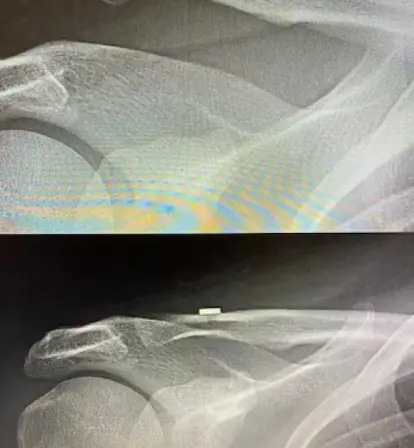

Joint replacement begins with careful evaluation and planning. Clinical examination and imaging help understand the extent of joint damage and determine the most suitable approach for each patient.